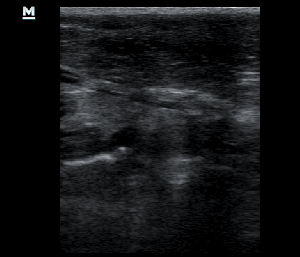

The spleen was increased in size with a diffuse parenchymal hyperechogenicity. A small section of the small intestine was enlarged with loss of its normal wall layers (pic1). The surrounding fat tissue was also hyperechoic. An enlarged regional mesenteric lymphnode was noted with diffuse hypoechogenicity. A Fine Needle Aspiration was performed in order to collect cytology speciments from the spleen and the intestinal lesions. The diagnose was alimentary tract lymphoma.

Image series, through the normal anatomy, to the lesion of the small intestine, in a perpendicular view.